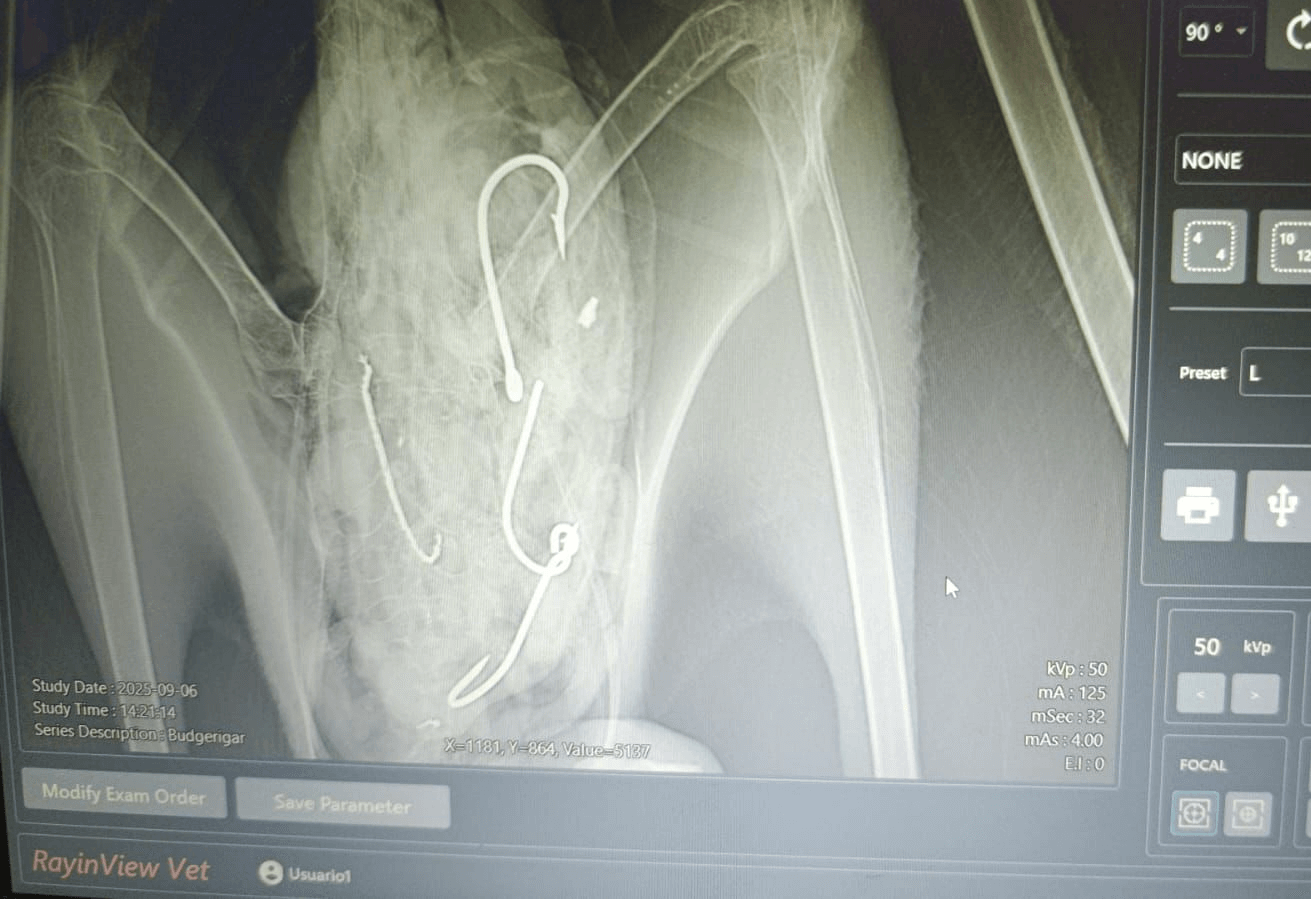

萨氏信天翁 X 射线。图片:uux.cn/Ruben Aleman,Fundación Juvimar。

(神秘的地球uux.cn)据《大众科学》(劳拉·拜萨斯):一种罕见的海鸟正在从一次成功且挽救生命的手术中恢复过来。厄瓜多尔安孔西托的一名渔民在发现幼年萨氏信天翁看起来不适后发现了它。这只鸟吞下了四个大鱼钩和一些钓鱼线,被带到洛佩兹港接受康复和护理。当地兽医鲁本·阿莱曼 (Ruben Aleman) 从这只鸟身上取出了废弃的渔具。经过一番额外的 R&R,这只鸟于 10 月下旬在马纳比省附近的海滩上被释放。

“通过与厄瓜多尔环境部当地代表 (REMACOPSE) 和一名专业兽医的协调,我们成功地从这只鸟身上取下了四个鱼钩,其中包括一个对其食道造成伤害的鱼钩,”美国鸟类保护协会厄瓜多尔海鸟兼捕协调员乔瓦尼·苏亚雷斯·埃斯平 (Giovanny Suárez Espín) 在一份声明中说。

通过手术从萨氏信天翁身上取出的渔具。图片:uux.cn/Ruben Aleman,Fundación Juvimar。